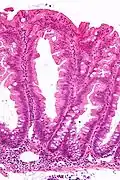

Intermediate magnification micrograph of an SSL.

Intermediate magnification micrograph of an SSL. -

SSLs are diagnosed by their microscopic appearance; histomorphologically, they are characterized by (1) basal dilation of the crypts, (2) basal crypt serration, (3) crypts that run horizontal to the basement membrane (horizontal crypts), and (4) crypt branching. The most common of these features is basal dilation of the crypts.

Unlike conventional colonic adenomas (e.g. tubular adenoma, villous adenoma), they do not (typically) have nuclear changes (nuclear hyperchromatism, nuclear crowding, elliptical/cigar-shaped nuclei).